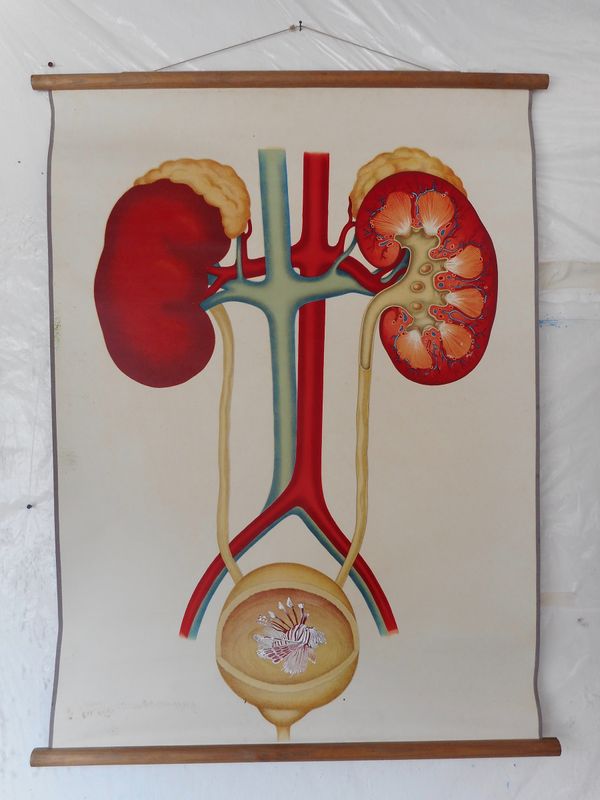

2018 - anatomy (kidneys)